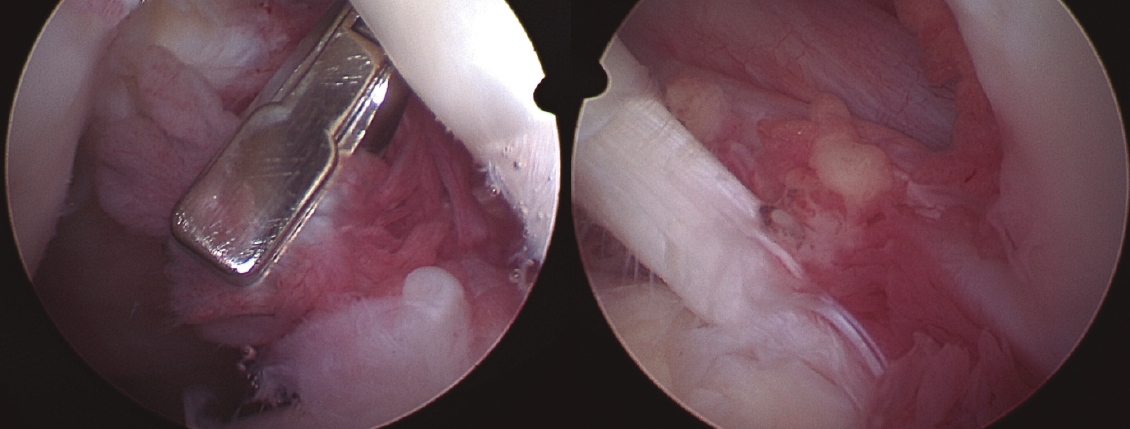

Todos los casos de hombro fueron tratados de manera artroscópica, y los hallazgos incluyeron la presencia de vellosidades características del LA (Figura 3), así como roturas en el seno del manguito rotador. Esta sinovitis proliferativa de aspecto graso se ubicaba predominantemente en la zona del intervalo rotador y en la periferia de la glena e inserción del tendón de la porción larga del bíceps.

Figura 3. Imágenes artroscópicas de las vellosidades del LA en el hombro, así como los cambios artrósicos en la articulación glenohumeral.

En los casos de la rodilla, con una intervención abierta (en el contexto de la colocación de una prótesis total de rodilla) y otra artroscópica, su localización fue predominantemente suprapatelar, si bien también se encontraron vellosidades (Figura 4).

Figura 4. Imágenes artroscópicas del LA en la rodilla, con presencia de vellosidades grasas en el receso suprapatelar e incluso en la zona supra- e inframeniscal.